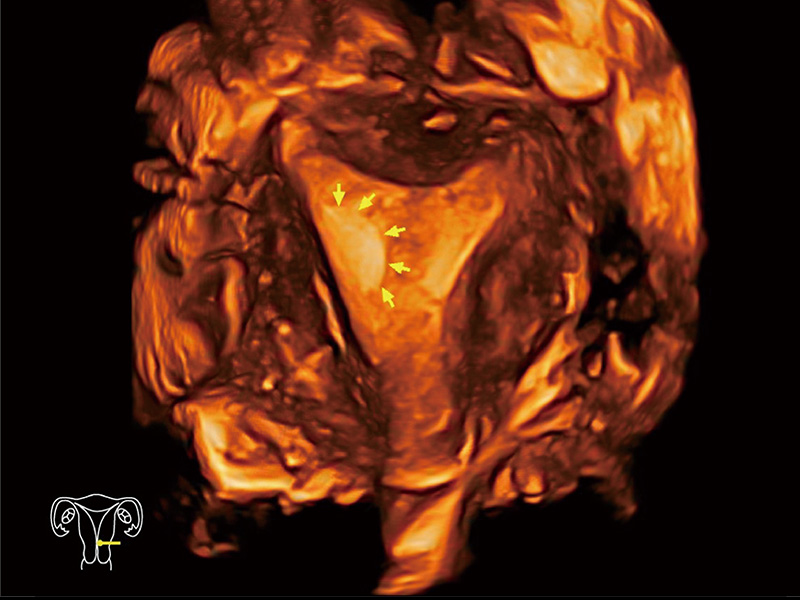

“生育问题”即关系民族复兴,也关系亿万家庭的幸福。随着婚育年龄推迟、社会压力增加等因素,越来越多人群也面临着“生不出、生不好”的问题。辅助生殖作为治疗不孕不育最有效的方法之一,也逐渐成为育儿新希望。而超声检查能为生殖需求人群的初诊评估提供宝贵的信息。 P20 Elite是新葡的京集团8814检测站匠心打造的一款生殖应用型彩超。她继承新葡的京集团8814检测站高端极光平台,突破性地将多款新型芯片及硬件模块进行整合,均衡了高端系统性能与小巧灵动机身。P20 Elite卓越的图像质量搭载专科探头,旨在为您提供全面的辅助生殖解决方案。

P20 Elite配备了丰富的生殖探头群和临床应用功能,在卵泡监测、穿刺取卵、胚胎移植、妊娠确认等领域,为生殖需求人群提供了新的临床机会,重新定义高端超声如何应用于生殖健康检查。